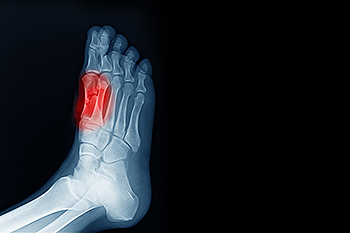

Due to the wide variety of potential causes of ankle pain, podiatrists will utilize a number of different methods to properly diagnose ankle pain. This can include asking for personal and family medical histories and of any recent injuries. Further diagnosis may include sensation tests, a physical examination, and potentially x-rays or other imaging tests.

Sesamoid Fracture Treatment

To conduct a diagnosis, the podiatrist will examine the ball of the foot and big toe. They will look for any outliers and check the movement of the toe. X-rays will be taken to rule out any other conditions and ensure that it is sesamoiditis.